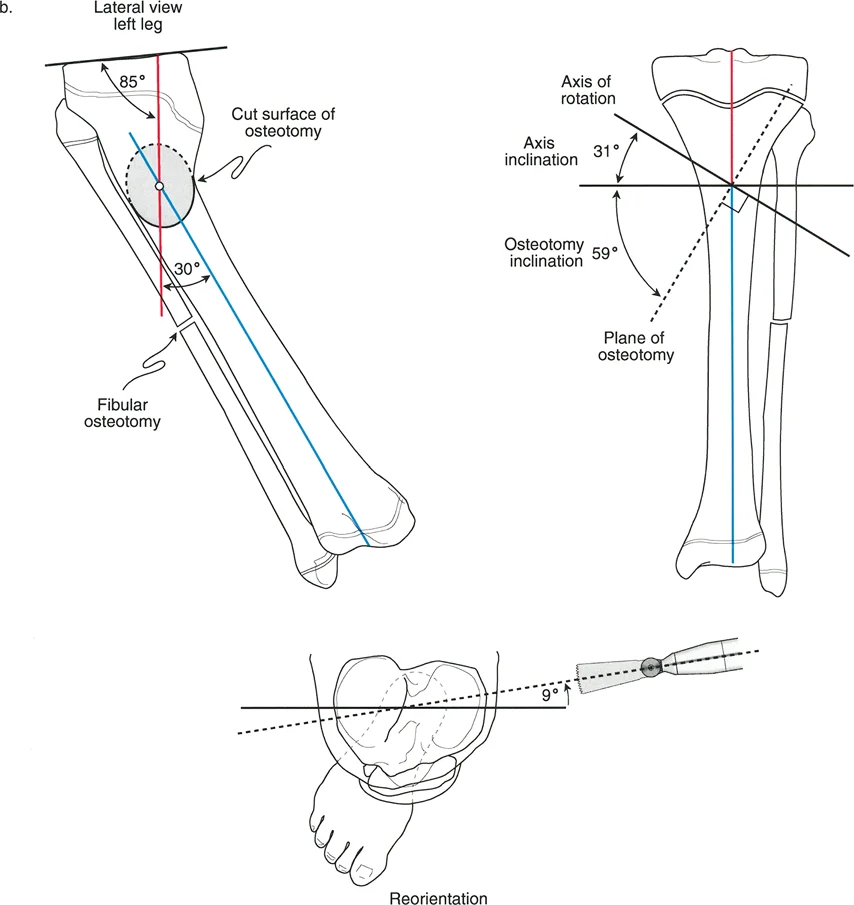

- جراحات قطع العظم وتقويم المحاور

لطالما كان التركيز الأساسي في جراحة العظام، خاصة لطلبة الجراحة، ينصب على التشوهات الثابتة للأطراف السفلية. هذه التشوهات تشمل انحرافات العظام الثابتة، والتئام العظام بشكل خاطئ، وعدم التئامها، وتيبس المفاصل، وهي حالات يسهل قياسها وتحديدها عبر الأشعة السينية الثابتة. ولكن، لكي يتقن الجراح حقًا إعادة بناء الأطراف السفلية، وتخطيط عمليات قطع العظم (Osteotomy)، وجراحات استبدال المفاصل المعقدة، يجب عليه أن يتجاوز هذا الفهم التقليدي ويتعمق في العالم الحركي والسائل للتشوهات الديناميكية.

في حين أن التشوهات الديناميكية تُناقش غالبًا في سياق أمراض الأعصاب والعضلات لدى الأطفال، فإن المبادئ البيوميكانيكية التي تحكمها تنطبق عالميًا على إعادة بناء العظام لدى البالغين. يشمل ذلك سيناريوهات إعادة البناء المعقدة للغاية، مثل استبدال مفصل الركبة الكلي (TKR) واستبدال مفصل الورك الكلي (THR) المرتبطة بالانحرافات الشديدة خارج المفصل. إن فهم الأذرع الرافعة هو المتطلب الأساسي لإتقان هذه التقنيات المتقدمة في جراحة المفاصل وقطع العظم، وهو ما يتقنه الأستاذ الدكتور محمد هطيف في ممارسته اليومية.

بينما لا يستطيع الطب الحديث فعل الكثير لزيادة القوة البيولوجية الخام التي تولدها العضلة بشكل دائم (بخلاف العلاج الطبيعي)، يمكن غالبًا زيادة حجم العزم المؤثر على المفصل بشكل كبير ببساطة عن طريق تصحيح خلل وظيفة الذراع الرافعة جراحيًا. هذا هو جوهر النهج الذي يتبعه الأستاذ الدكتور محمد هطيف في علاج التشوهات العظمية المعقدة، حيث يركز على استعادة الميكانيكا الحيوية السليمة للجسم.